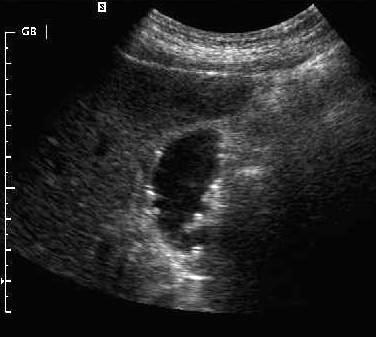

Emphysematous Cholecystitis

Gas forming bacteria in gallbladder wall yields to high intensity echoes and comet tail artifact